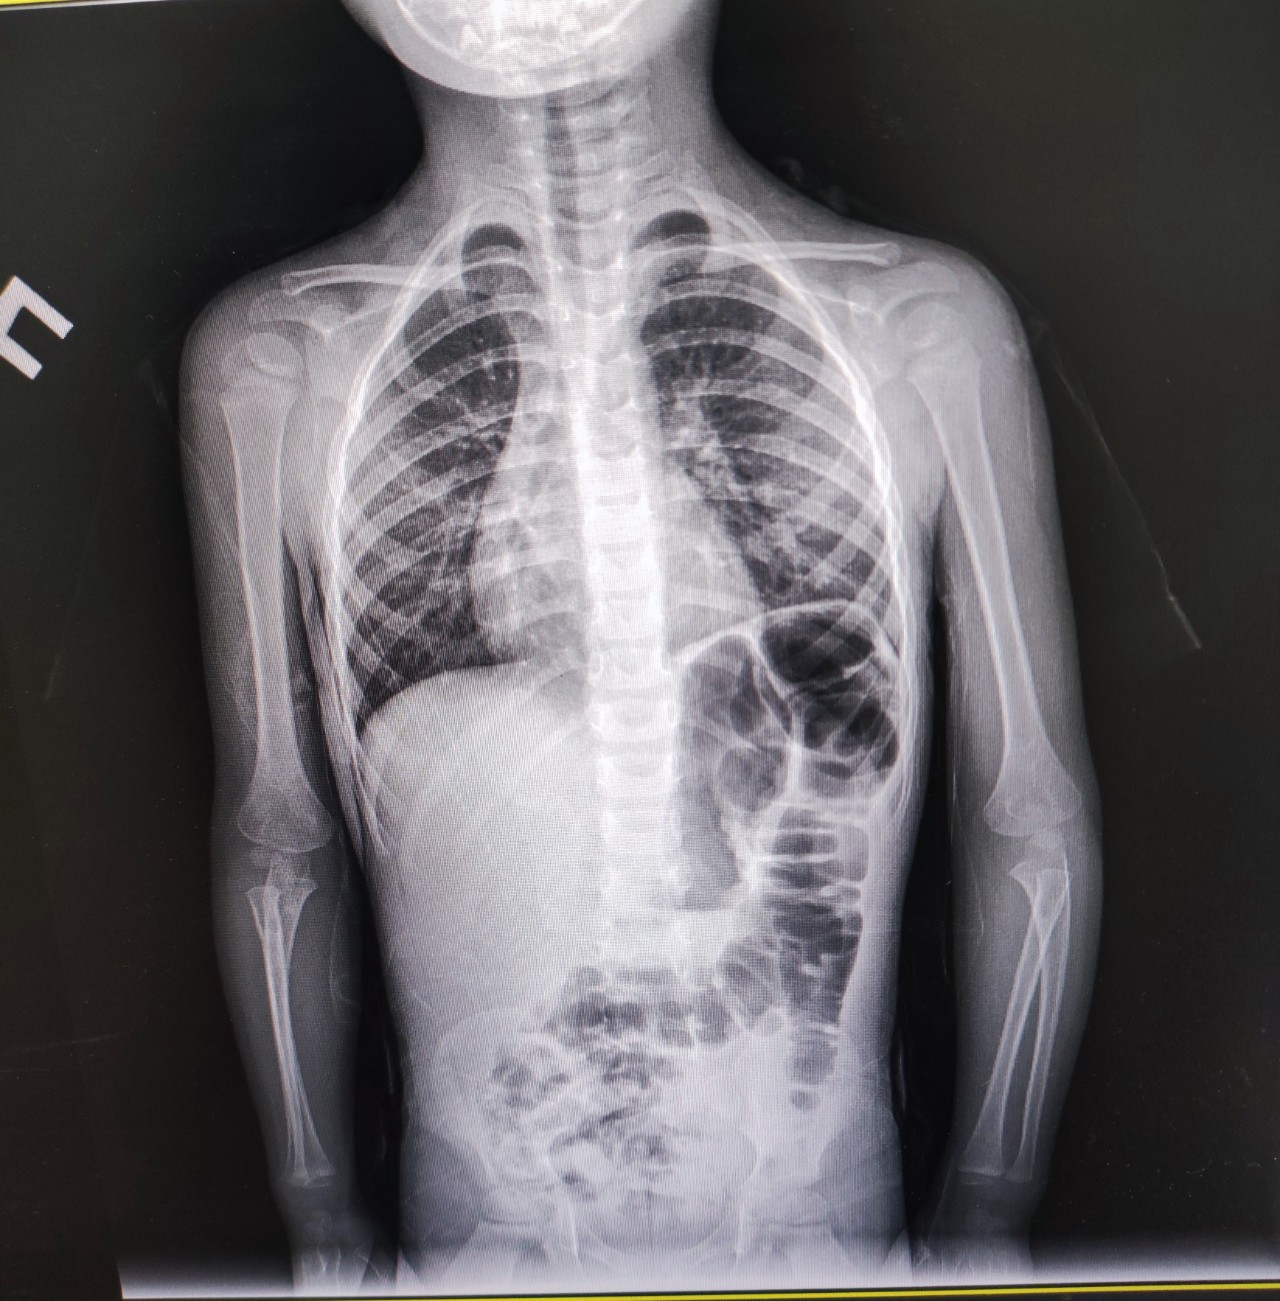

Вітаю, дитина хворіє другий раз поспіль, перший раз пропили антібіотік аугментін (у зв'язку з важким диханням), вийшли у садочок піднялась ввечері температури 39, лікар сказав що це новий вірус через 5 днів приписали Сумамед, пропили 5 днів, температура трималась, зробили знімок і здали ЗАК, підвищені лейкоцити 13,2, ставлять бронхіт, не має ли на знімку пневманії, і наскільки сильний бронхіт?

Вітаю! Пневмония слева не исключена, нужен левый боковой снимок и курс антибиотиков инъекционных, желательно в стационаре. Боли в животе есть? Запоры, поносы? Сыпь?

Спасибо за ответ, сыпи нет, живот не болит, стул густой как пластилин, но в туалет ходит регулярно(каждый день 1-2 раза), сегодня 3 дня как принимаем Сорцеф(суспензия), кашель прошёл вообще, активность ребенка стало нормальной, появился аппетит, но температура 37,8 ещё вчера была(поднимается только вечером), сегодня 37,2, осталось сильная заложенность носа без соплей (ничего не помогает)

Антибиотики все же сработали. Добавляем Баксет в возрастной дозировке и Иммупрет для восстановления